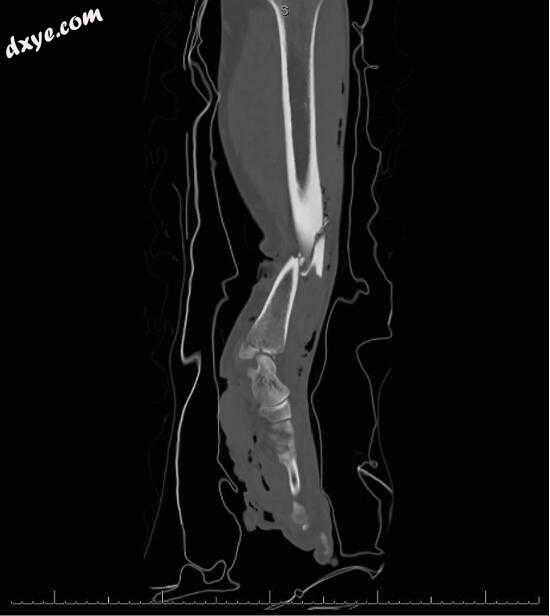

一名健康的40岁男子在高能量事故后出现在急诊室,左下肢和足部出现多处骨折和全面的软组织缺损。参见图1.在临床检查结合X线图像和左下肢CT扫描后,确定了以下骨折:Gustilo IIIB级骨折,内踝骨折,Tillaux-Chaput骨折,胡桃夹骨骨折长方体,舟骨的撕脱性骨折,第三,第四和第五跖骨头的骨折,第三近节指骨的中轴骨折和第一和第二近节指骨的基底骨折。参见图2.在补充在线图1中,显示左小腿和脚的CT扫描。保留了脚趾的主动伸展和屈曲,以及脚趾和前脚的敏感性。在脚底发现了不适的触觉和疼痛感。没有发现隔室综合征的迹象。

1.jpg

图1。

左小腿伤口的术前(足底,足底和小腿内侧的软组织缺损)。

2.jpg

图2。

骨折的X射线照片。